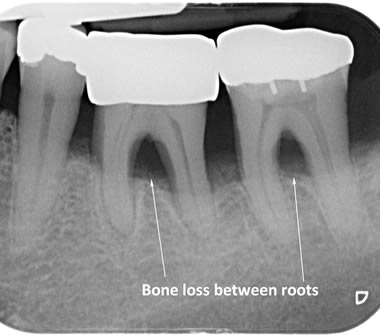

Periodontitis is a more advanced stage of gum disease where there has been damage to the bone which supports the teeth. If left untreated periodontitis leads to more and more bone loss until the teeth start to become loose and eventually fall out by themselves or need to be extracted by a Dentist.

The main cause of gum disease is plaque. Plaque consists of millions of bacteria which live on and around the teeth and gums. These bacteria produce toxins which damage the gums. To begin with the gums start to peel away from the teeth and “pockets” form. As the bacteria penetrate deeper into these “pockets” they then start to cause damage to the bone which holds the teeth in. As more bone loss occurs the teeth start to become increasingly looser until they eventually start to fall out one by one.

The diagrams below show the different stages of gum disease